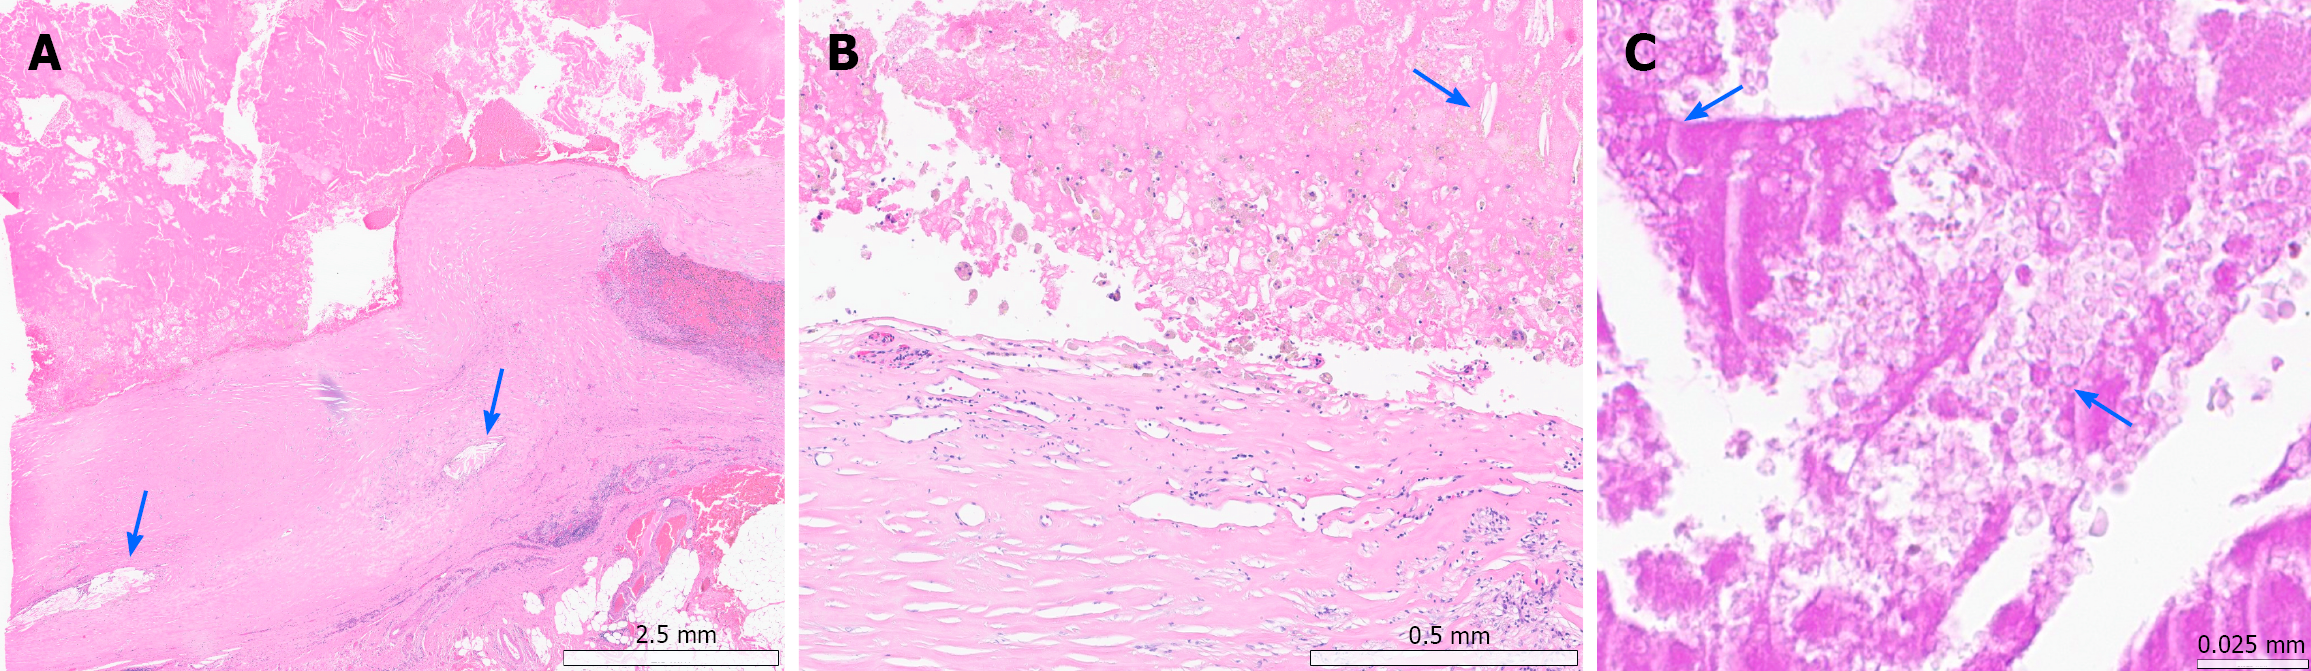

Microscopically, low-power examination demonstrated a thick fibrous cyst wall located within the subserosal layer and attached to the pericolic adipose tissue (Figure 4A). The cyst lacked an epithelial lining, and the wall was composed of densely hyalinized collagen with mild chronic inflammatory cell infiltration, including lymphocytes and histiocytes. Scattered cholesterol crystals were identified within the cyst wall and intracystic contents, accompanied by a foreign-body-type granulomatous reaction. High-power examination revealed dense fibrosis with focal infiltration of macro

| Postoperative pathology | Final diagnosis | Well-circumscribed 9.7 cm × 8.0 cm × 7.5 cm subserosal mass arising from the transverse colon; unilocular cystic lesion with a thick fibrous capsule, containing necrotic debris and old hemorrhage. No epithelial lining or neoplastic cells identified. Histology demonstrated cholesterol crystals and chronic foreign body-type inflammatory reaction, with PAS-positive irregular foreign materials detected microscopically, despite no grossly identifiable foreign material |

Postoperative inflammatory pseudocyst (PIP) is an important differential diagnosis, as it is a chronic cystic lesion characterized by a fibrous wall, absence of epithelial lining, and intracystic necrotic debris following abdominal surgery or peritonitis[7,12]. These features were present in our case, and the history of perforated appendicitis supports a postoperative inflammatory background. However, the identification of irregular PAS-positive foreign materials within the necrotic contents, together with cholesterol crystals and a foreign body-type reaction, favors a chronic foreign body–associated process rather than conventional PIP[6,8]. Although no gross foreign material was identified, long-standing foreign substances may fragment over time and persist only as microscopic remnants[1,10]. Accordingly, this lesion is best classified as a foreign body-associated reactive mass within the postoperative inflammatory spectrum.